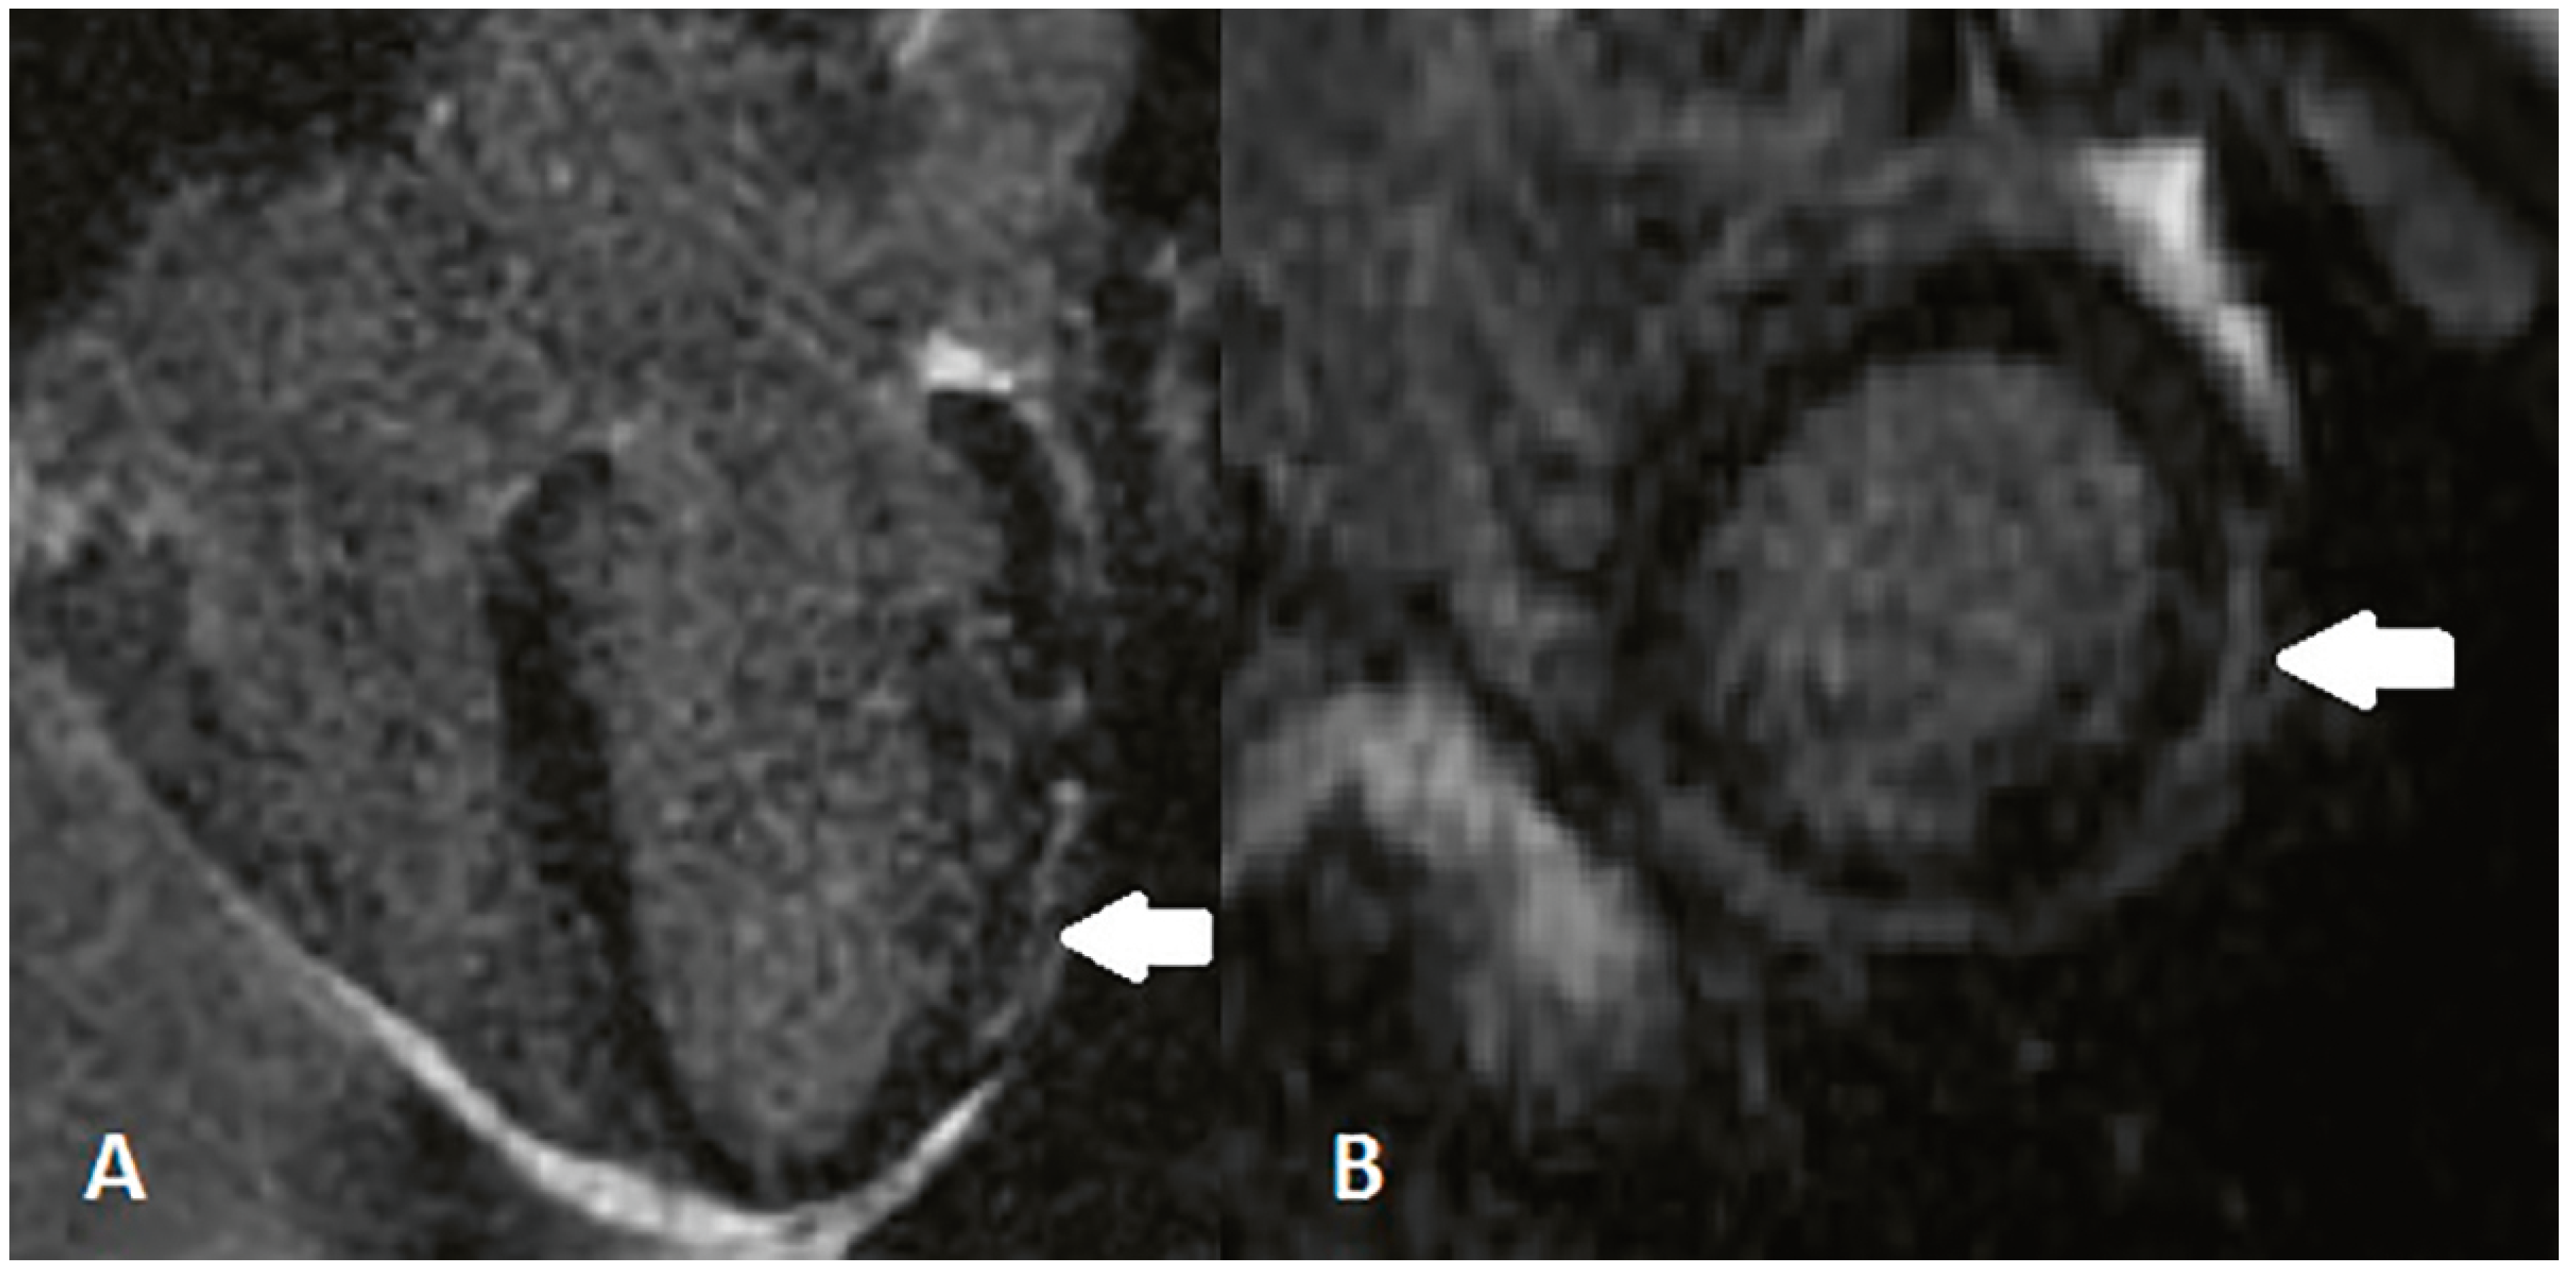

- Patient 1

- Patient 2